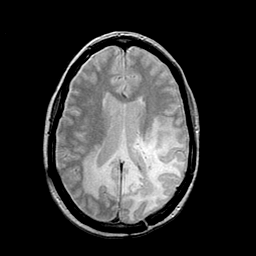

MR Study #2 -- Slice #32

[Home][Help][Clinical][Tour 1][Tour 2][Tour 3] Slice 32